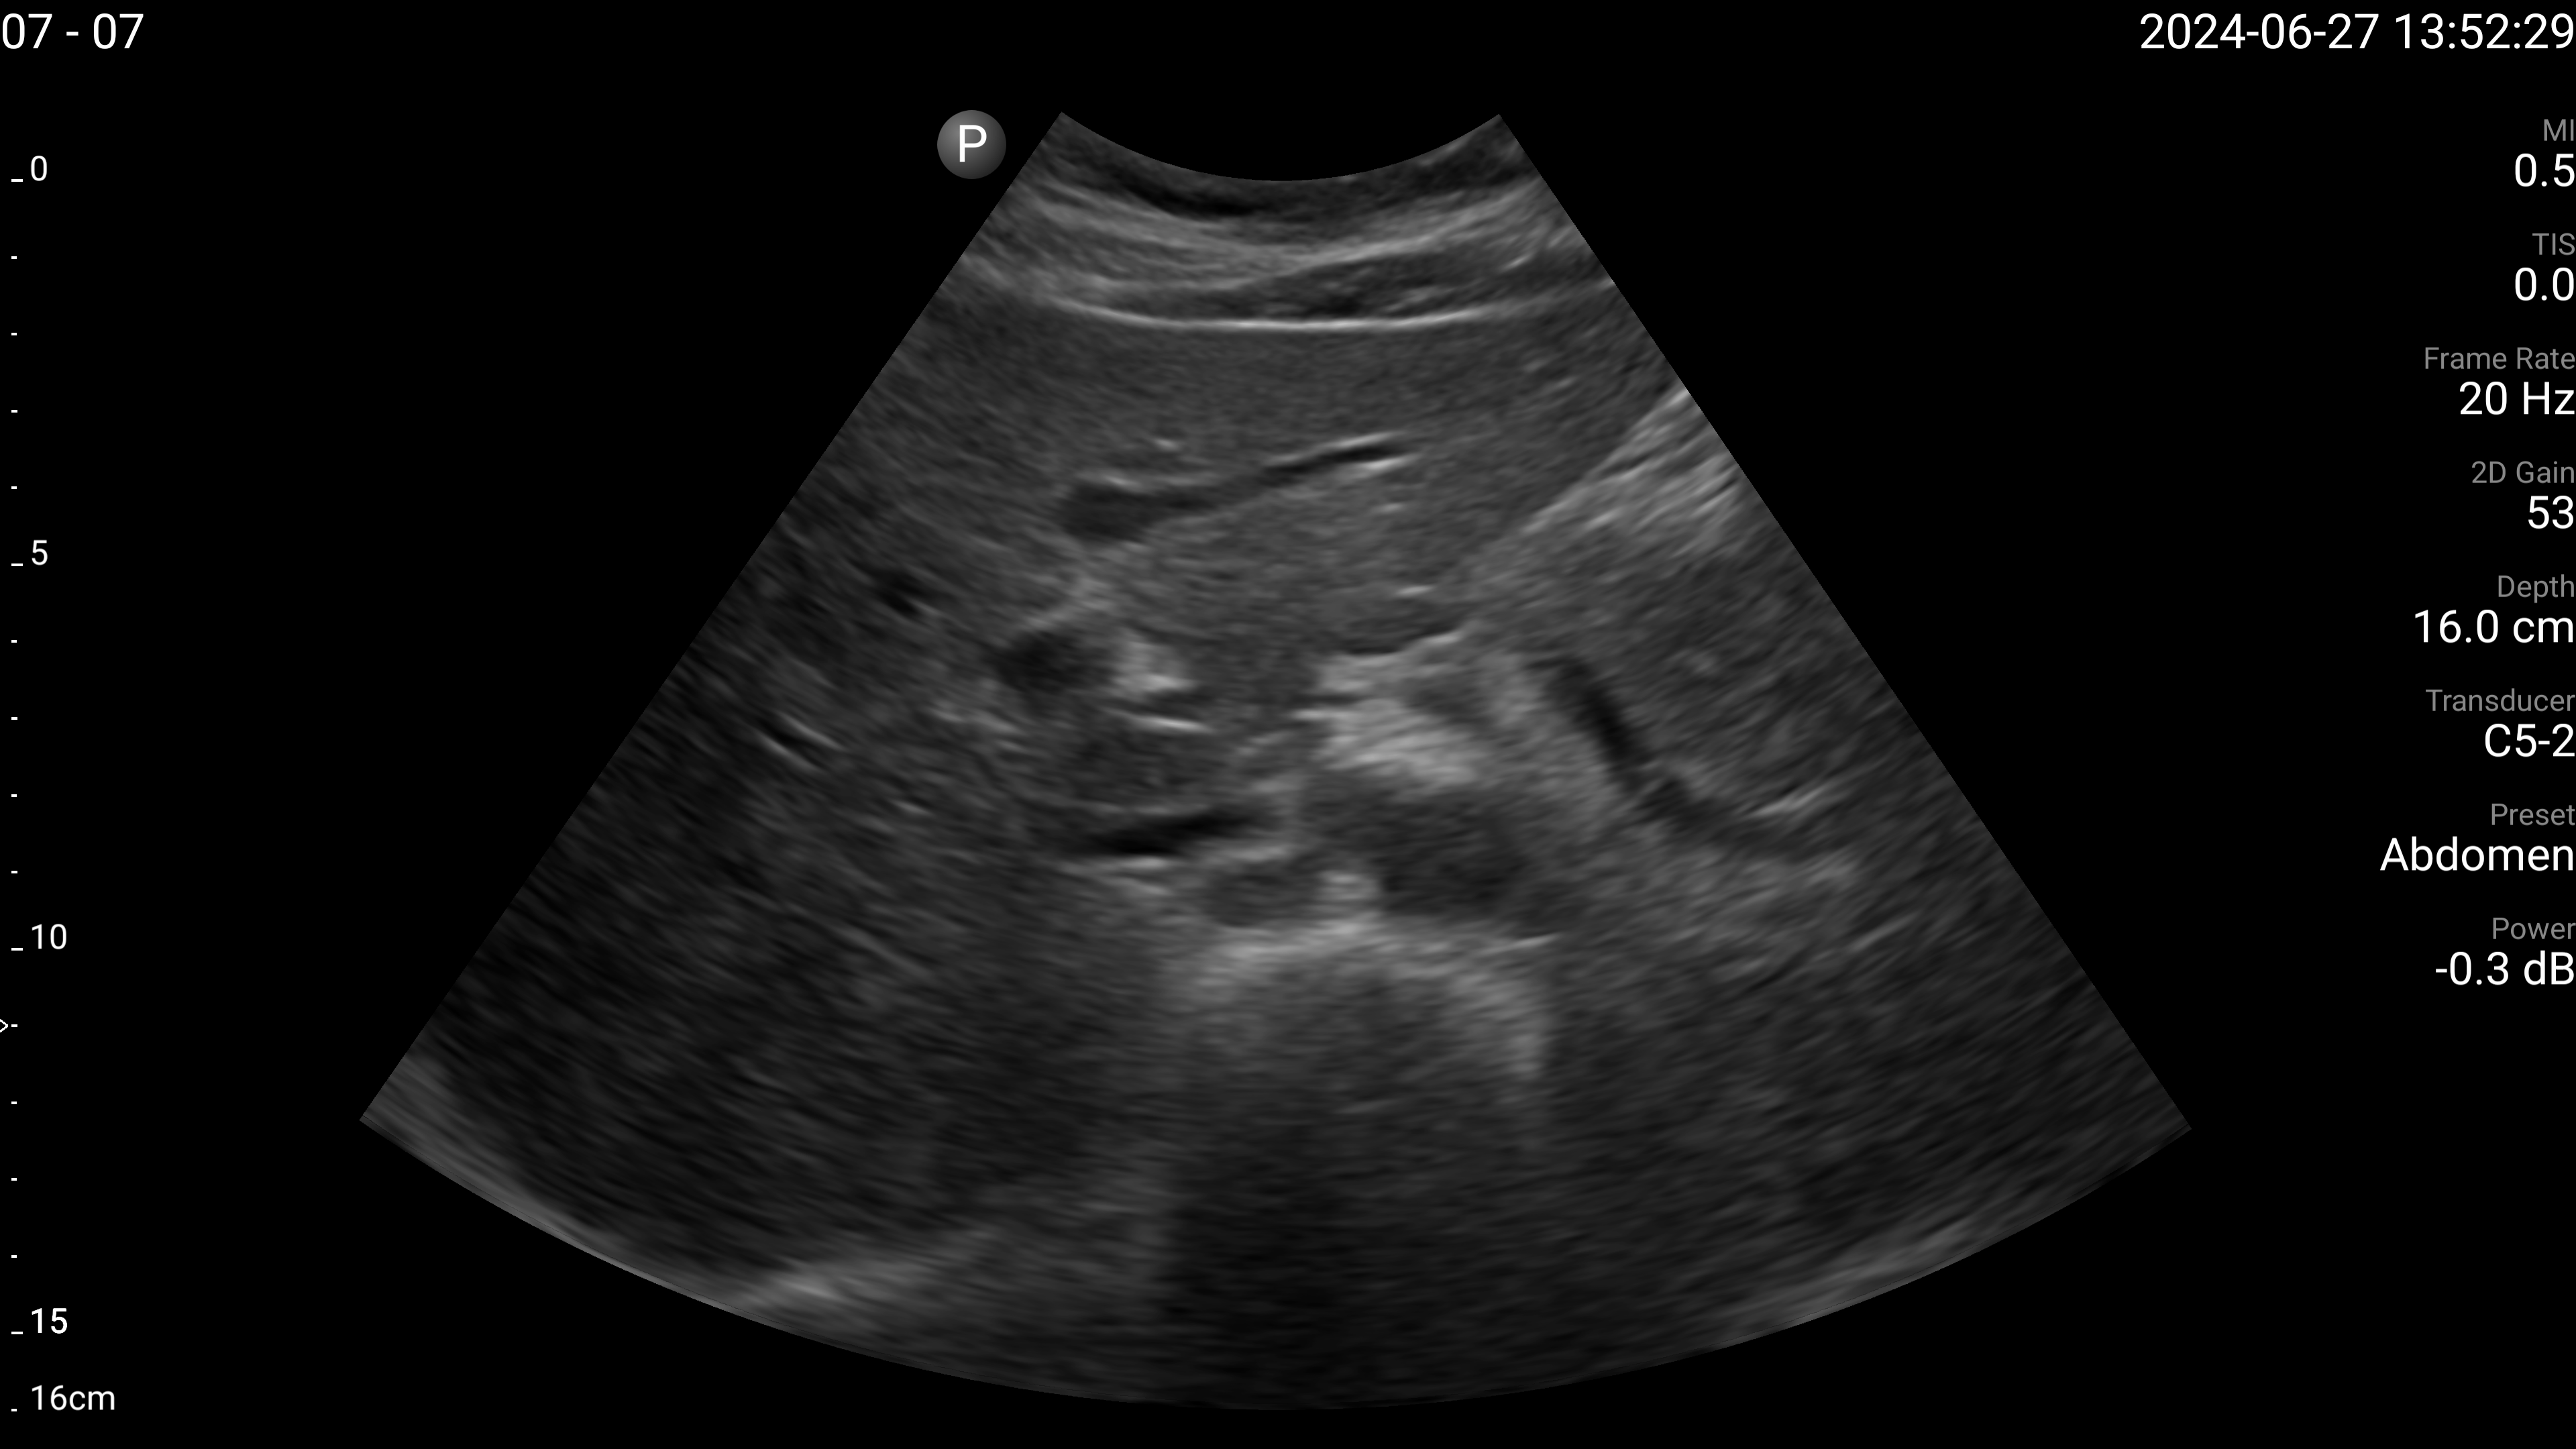

Refer to caption

(b) IVC - longitudinal.

Figure 4: Examples of the target US images acquired by the sonographers using the human teleoperation system.

The sonographers completed 11 abdominal US scans, each with 5 target images and measurements for a total of 55 images. An example image of each of the targets acquired during these tests is shown in Fig. 4. After completing the scans, two radiologists scored the images based on quality, including identifying targets that could not be seen or were not captured (which were given a score of 0). The distribution of these scores is illustrated in Fig. 5. The first radiologist identified 4 out of the 55 targets as not visible, while the second radiologist identified 6 out of 55 as not visible. Combined, this accounted for 7 unique targets that at least one radiologist considered missing. Of these missing targets, three were not captured due to large amounts of bowel gas and body habitus while one was seen but the sonographer did not capture and save the image. When excluding all the missing targets, the images obtained a mean score of 4.28±0.95plus-or-minus4.280.954.28\pm 0.95 out of 5 and 91.7% of the images were scored 3 or higher by both radiologists. A score of 3 or higher indicated the image quality was sufficient for basic image interpretation. 31.3% of the images were scored 5 by both radiologists, indicating the image quality was good and meaningful image interpretation was easy.